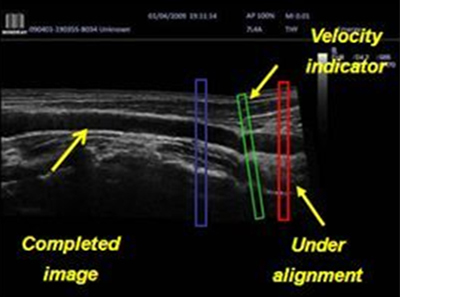

iScape™ (Real-time Panoramic Imaging)

Get a complete and extended view of the anatomical structure through panoramic imaging, coupled with velocity indication and forward/backward scan ability making scanning much easier, smoother and more controllable.